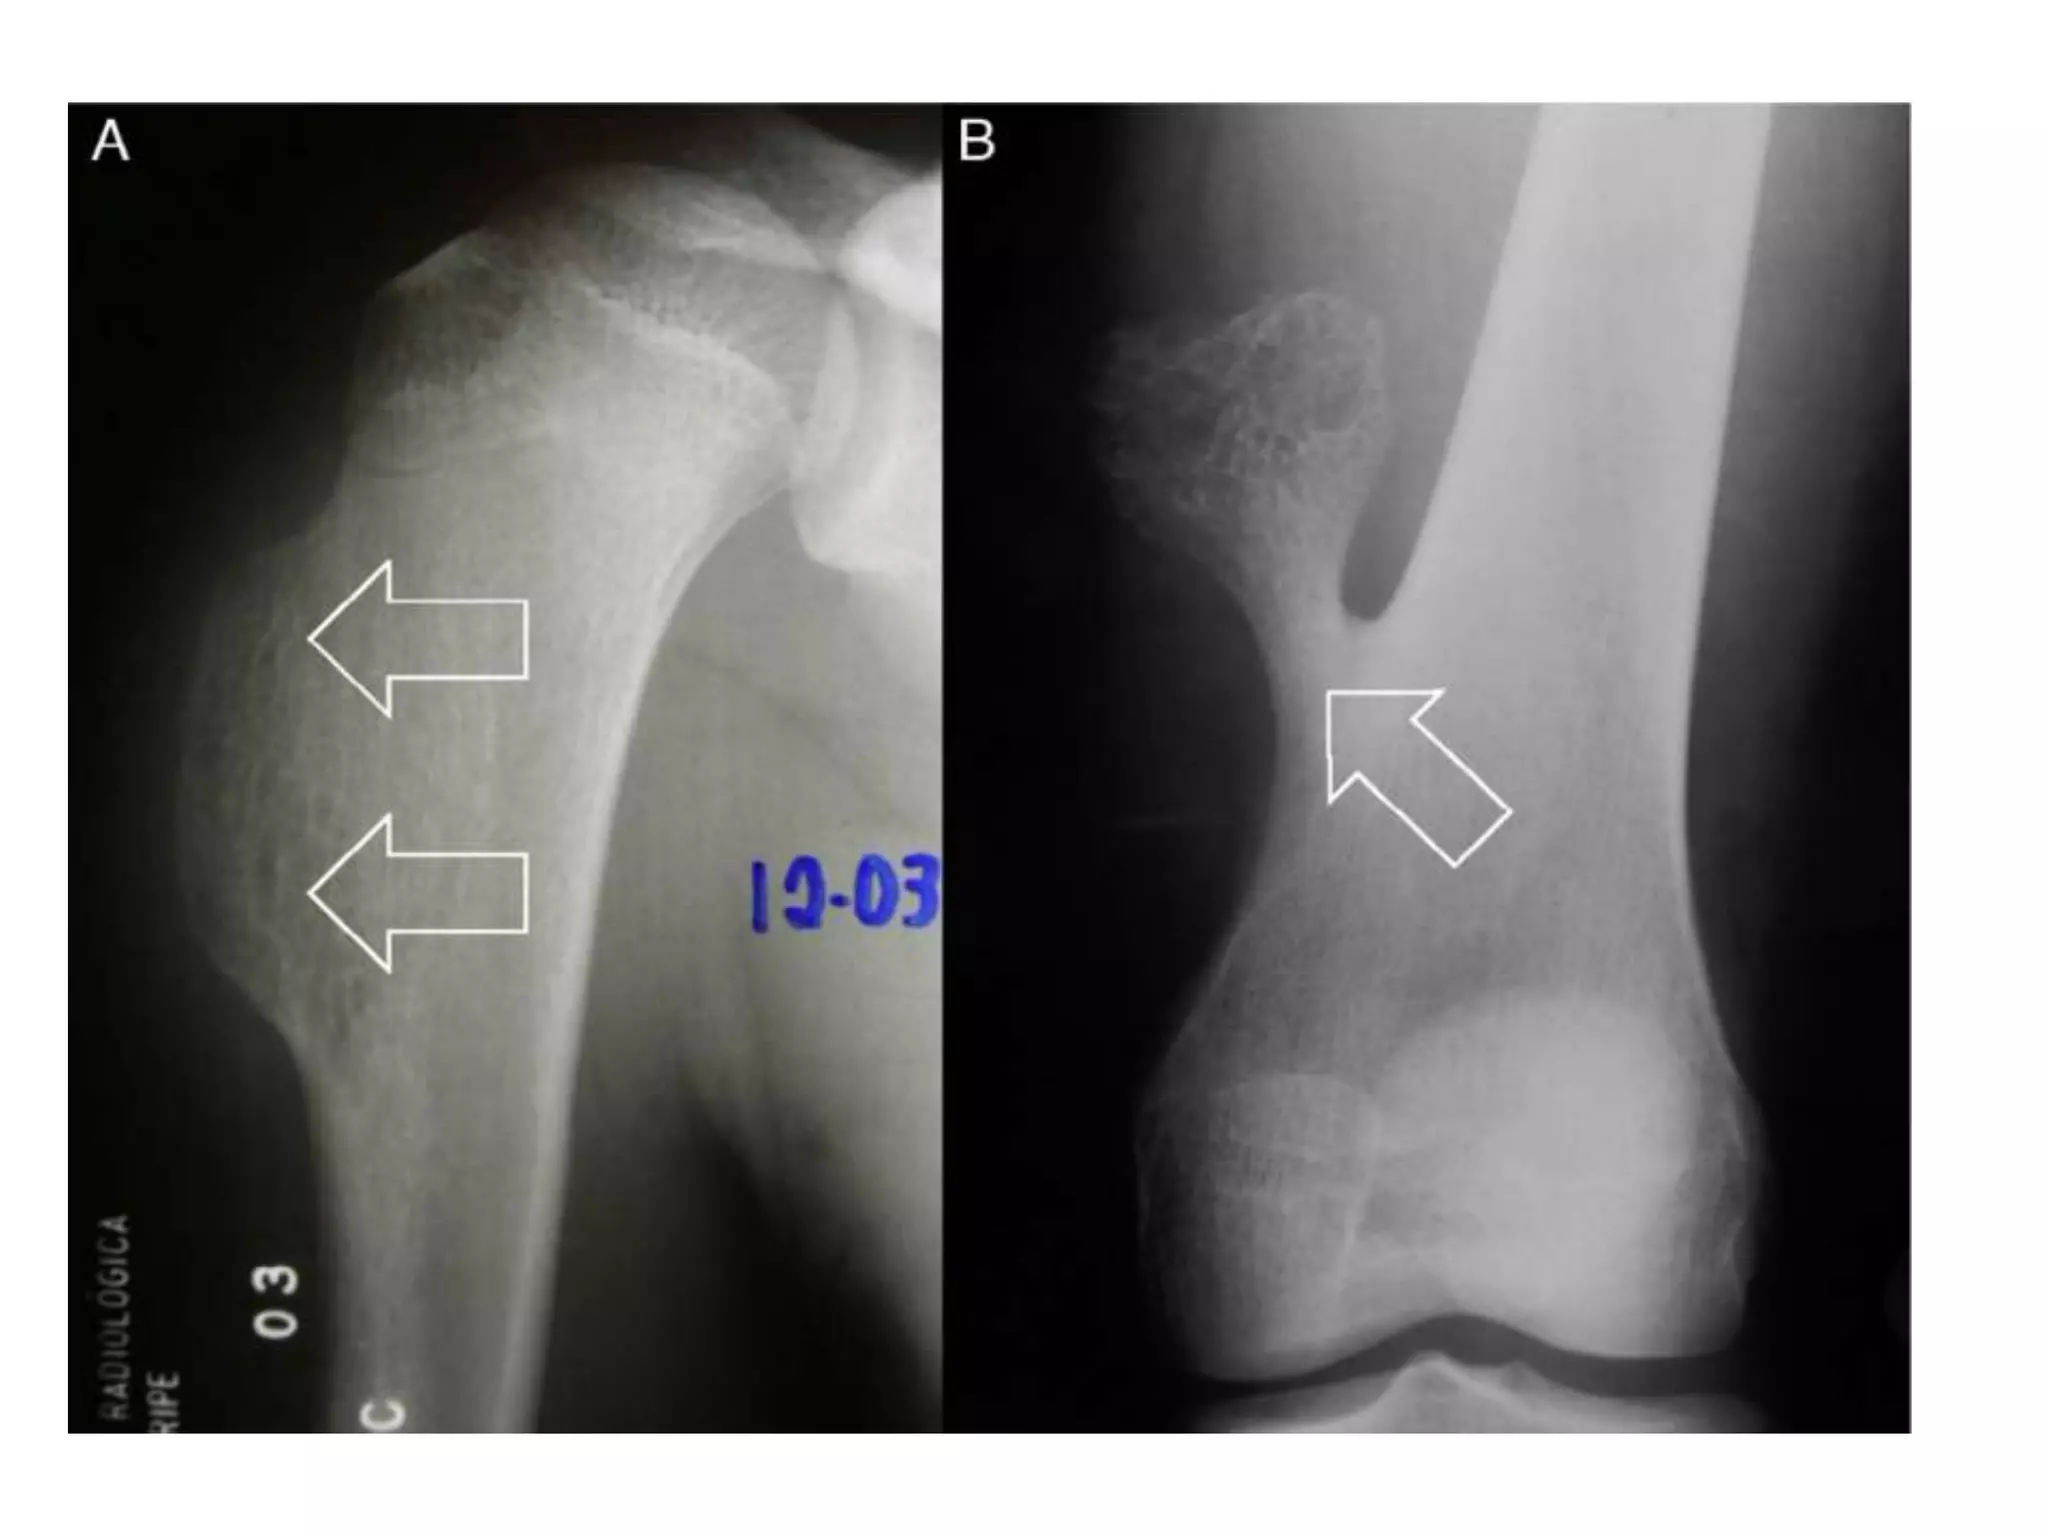

Radiological Findings

 hazy osteolytic areas which may alternate with unusually dense

osteoblastic areas.

 Area of irregular destruction in metaphysis, sometimes

overshadowed by new bone formation

 Erosion of cortex overlying lesion

 There may be also a poorly define endosteal margin.

 Periosteal reaction : Tumor lifts the periosteum which is

irregular , smooth layer in OM

 Codman’s triangle: Reactive new bone formation at the angles

of periosteal elevation.

 Sun- ray appearance/Sunburst effect: Growing tumor grows into

the overlying soft tissues, bone laid down along blood vessels

within tumor growing centrifugally

Chest X ray: to detect lung metastasis.

MRI and CT can be done: soft tissue spread

Bone scan: intramedullary spread (skip lesion)